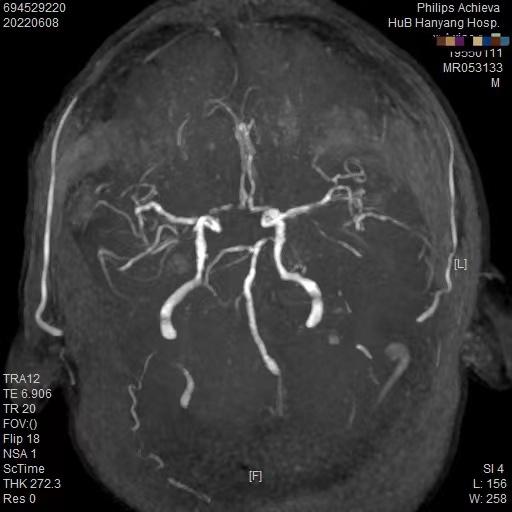

病例A :25岁的年轻人,头晕1周,前来就诊。起病后自行在网上查,觉得就是没休息好,后来又发现像“颈椎病”,觉得自己年轻,调整一下就恢复了。结果1周了,还是晕,上网搜“是不是脑梗中风?”,心里开始发紧了。赶紧到医院指挥医生,“别问这多的,那些检查我都不做,我要做核磁,我要排除脑梗”。头部核磁结果出来了,“正常的,没有急性中风病灶”,说什么都不愿继续检查和治疗了,“我要去做理疗”。1周后患者再次来到诊室,“医生我晕还没有好,睡眠也不太好,晕也不想去参加活动……”,瞬间有点emo了,病人逐渐变成慢性头晕影响生活质量了。 病例B :67岁老年人,有高血压病史,头晕、眩晕1周就诊。一开始起病后症状不重,患者自认为“眩晕症发了”,*毛老**病,扛一扛,自己吃点眩晕的药就会好的。结果症状逐渐加重,开始出现走路不稳、右边手脚麻木,前来求治。头部核磁共振提示右侧小脑半球急性脑梗死,头颈部动脉硬化改变,右侧椎动脉闭塞(见下图),但急性期溶栓时间已过。